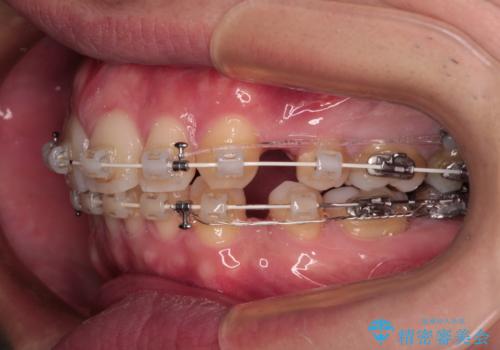

なるべく目立たない装置が希望だったため、審美装置で治療を行いました。

左上はアンカースクリューを併用することでスムーズに抜歯スペースを閉じることができました。